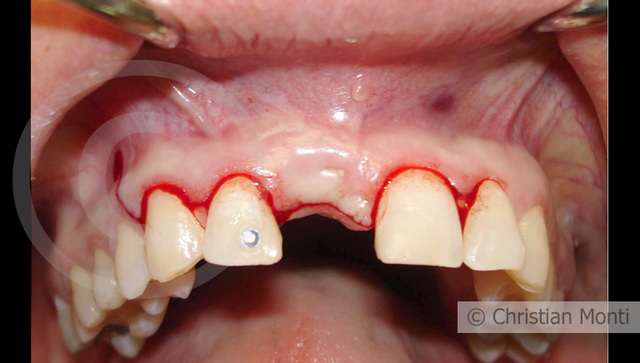

EDENTULIA SINGOLA

Impianto in sostituzione di un incisivo superiore